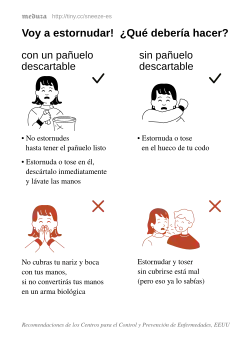

La transmisión del SARS-CoV-2 se produce mediante pequeñas gotas —microgotas de Flügge[23]— que se emiten al hablar, estornudar, toser o espirar, que al ser despedidas por un portador (que puede no tener síntomas de la enfermedad o estar incubándola)[24] pasan directamente a otra persona mediante la inhalación, o quedan sobre los objetos y superficies que rodean al emisor, y luego, a través de las manos, que lo recogen del ambiente contaminado, toman contacto con las membranas mucosas orales, nasales y oculares, al tocarse la boca, la nariz o los ojos.[25][26] También está documentada la transmisión por aerosoles ( < 5μm).[27][28] La propagación mediante superficies contaminadas o fómites (cualquier objeto carente de vida, o sustancia, que si se contamina con algún patógeno es capaz de transferirlo de un individuo a otro) no contribuye sustancialmente a nuevas infecciones.[29]

Los síntomas aparecen entre dos y catorce días (período de incubación), con un promedio de cinco días, después de la exposición al virus.[30][31][32][33] Existe evidencia limitada que sugiere que el virus podría transmitirse uno o dos días antes de que se tengan síntomas, ya que la viremia alcanza un pico al final del período de incubación.[34][35] El contagio se puede prevenir con el lavado de manos frecuente, o en su defecto la desinfección de las mismas con alcohol en gel, cubriendo la boca al toser o estornudar, ya sea con la sangradura (parte hundida del brazo opuesta al codo) o con un pañuelo y evitando el contacto cercano con otras personas,[25] entre otras medidas profilácticas, como el uso de mascarillas. La OMS desaconsejaba en marzo la utilización de máscara quirúrgica por la población sana,[36][37] en abril la OMS consideró que era una medida aceptable en algunos países.[38] No obstante, ciertos expertos recomiendan el uso de máscaras quirúrgicas basados en estudios sobre la Influenza H1N1, donde muestran que podrían ayudar a reducir la exposición al virus.[39] Los Centros para el Control y Prevención de Enfermedades (CDC) de Estados Unidos recomiendan el uso de mascarillas de tela, no médicas.[40] Recomendación de los CDC (febrero de 2021).[41]

Algunas organizaciones internacionales, como la OMS, han publicado medidas preventivas para reducir la transmisión del virus. Son similares a las que se han recomendado para prevenir la infección por otros coronavirus e incluyen:

- Lavarse frecuentemente las manos con agua y jabón.

- Al toser o estornudar, cubrirse la boca y la nariz con la sangría o fosa cubital (la concavidad que forma la cara interna del brazo al flexionarlo por el codo).

Para reducir las posibilidades de infectarse, las organizaciones sanitarias recomiendan evitar el contacto cercano con personas enfermas; lavarse las manos frecuentemente con agua y jabón; no tocarse los ojos, la nariz o la boca con las manos sin lavar; y practicar una buena higiene respiratoria.[177][30]

Las organizaciones de salud recomiendan cubrirse la boca y la nariz con el codo flexionado al toser o estornudar o cubrirse la boca y la nariz con un pañuelo desechable (que luego debe desecharse de inmediato) y a continuación lavarse las manos con un desinfectante de manos a base de alcohol o con agua y jabón.[30][184]

Si no hay una máscara disponible, cualquier persona que experimente síntomas respiratorios debe cubrirse con un pañuelo al toser o estornudar, desecharlo rápidamente en la basura y lavarse las manos. Si no está disponible un tejido, las personas pueden cubrirse la boca o la nariz con el codo flexionado.[30]